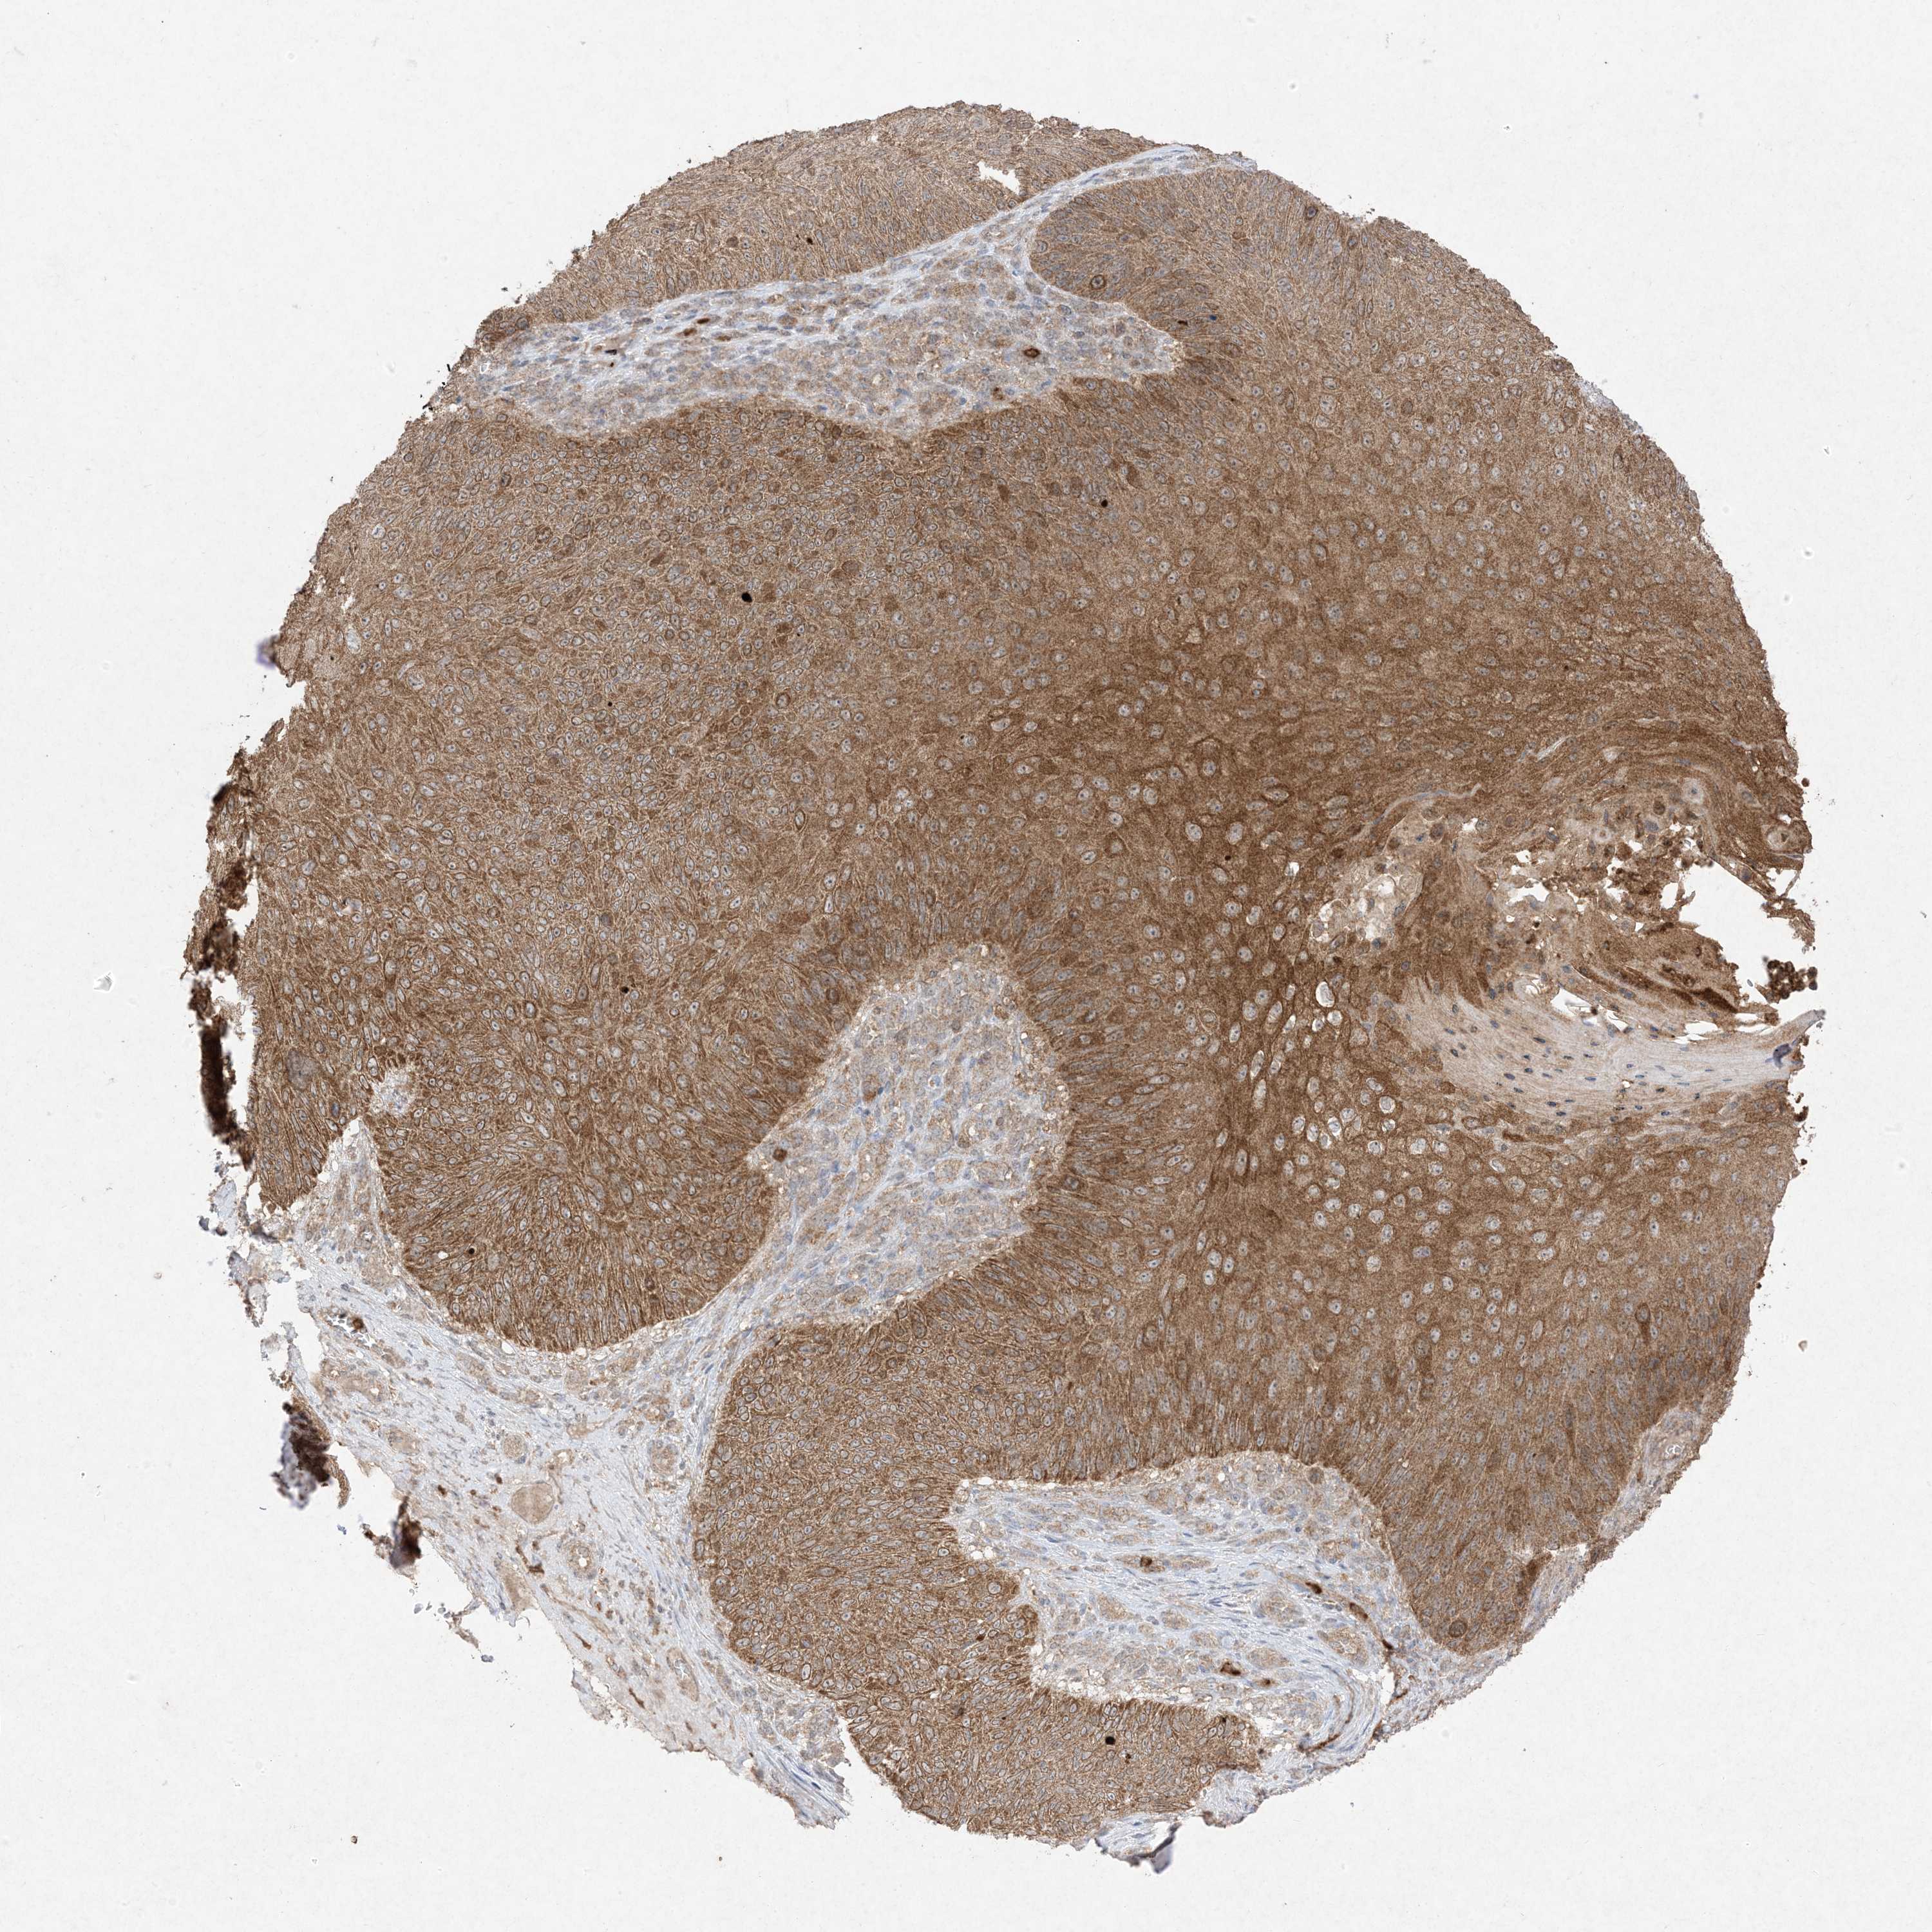

SKIN CANCER - Protein expressioni

A mouse-over function shows sample information and annotation data. Click on an image to view it in a full screen mode. Samples can be filtered based on level of antibody staining by selecting one or several of the following categories: high, medium, low and not detected. The assay and annotation is described here.

Each image is clickable and will lead to virtual microscopy that enables deeper exploration of all samples and also displays staining intensity scores, fraction scores and subcellular localization as well as patient and tissue information for each sample.

Antibody HPA054975

Antibody CAB011464

Antibody CAB035990

Antibody CAB080407

Staining

High

Medium

Low

Not detected

Squamous cell carcinoma, NOS